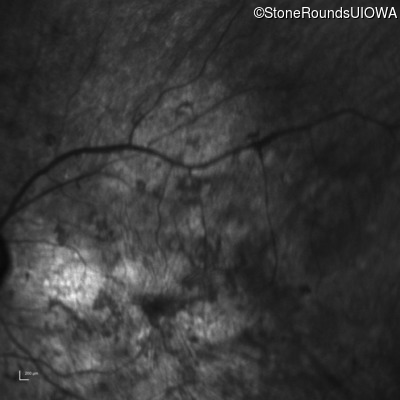

Infrared Fundus Photograph - Left - Hand Motion sc

Exemplar